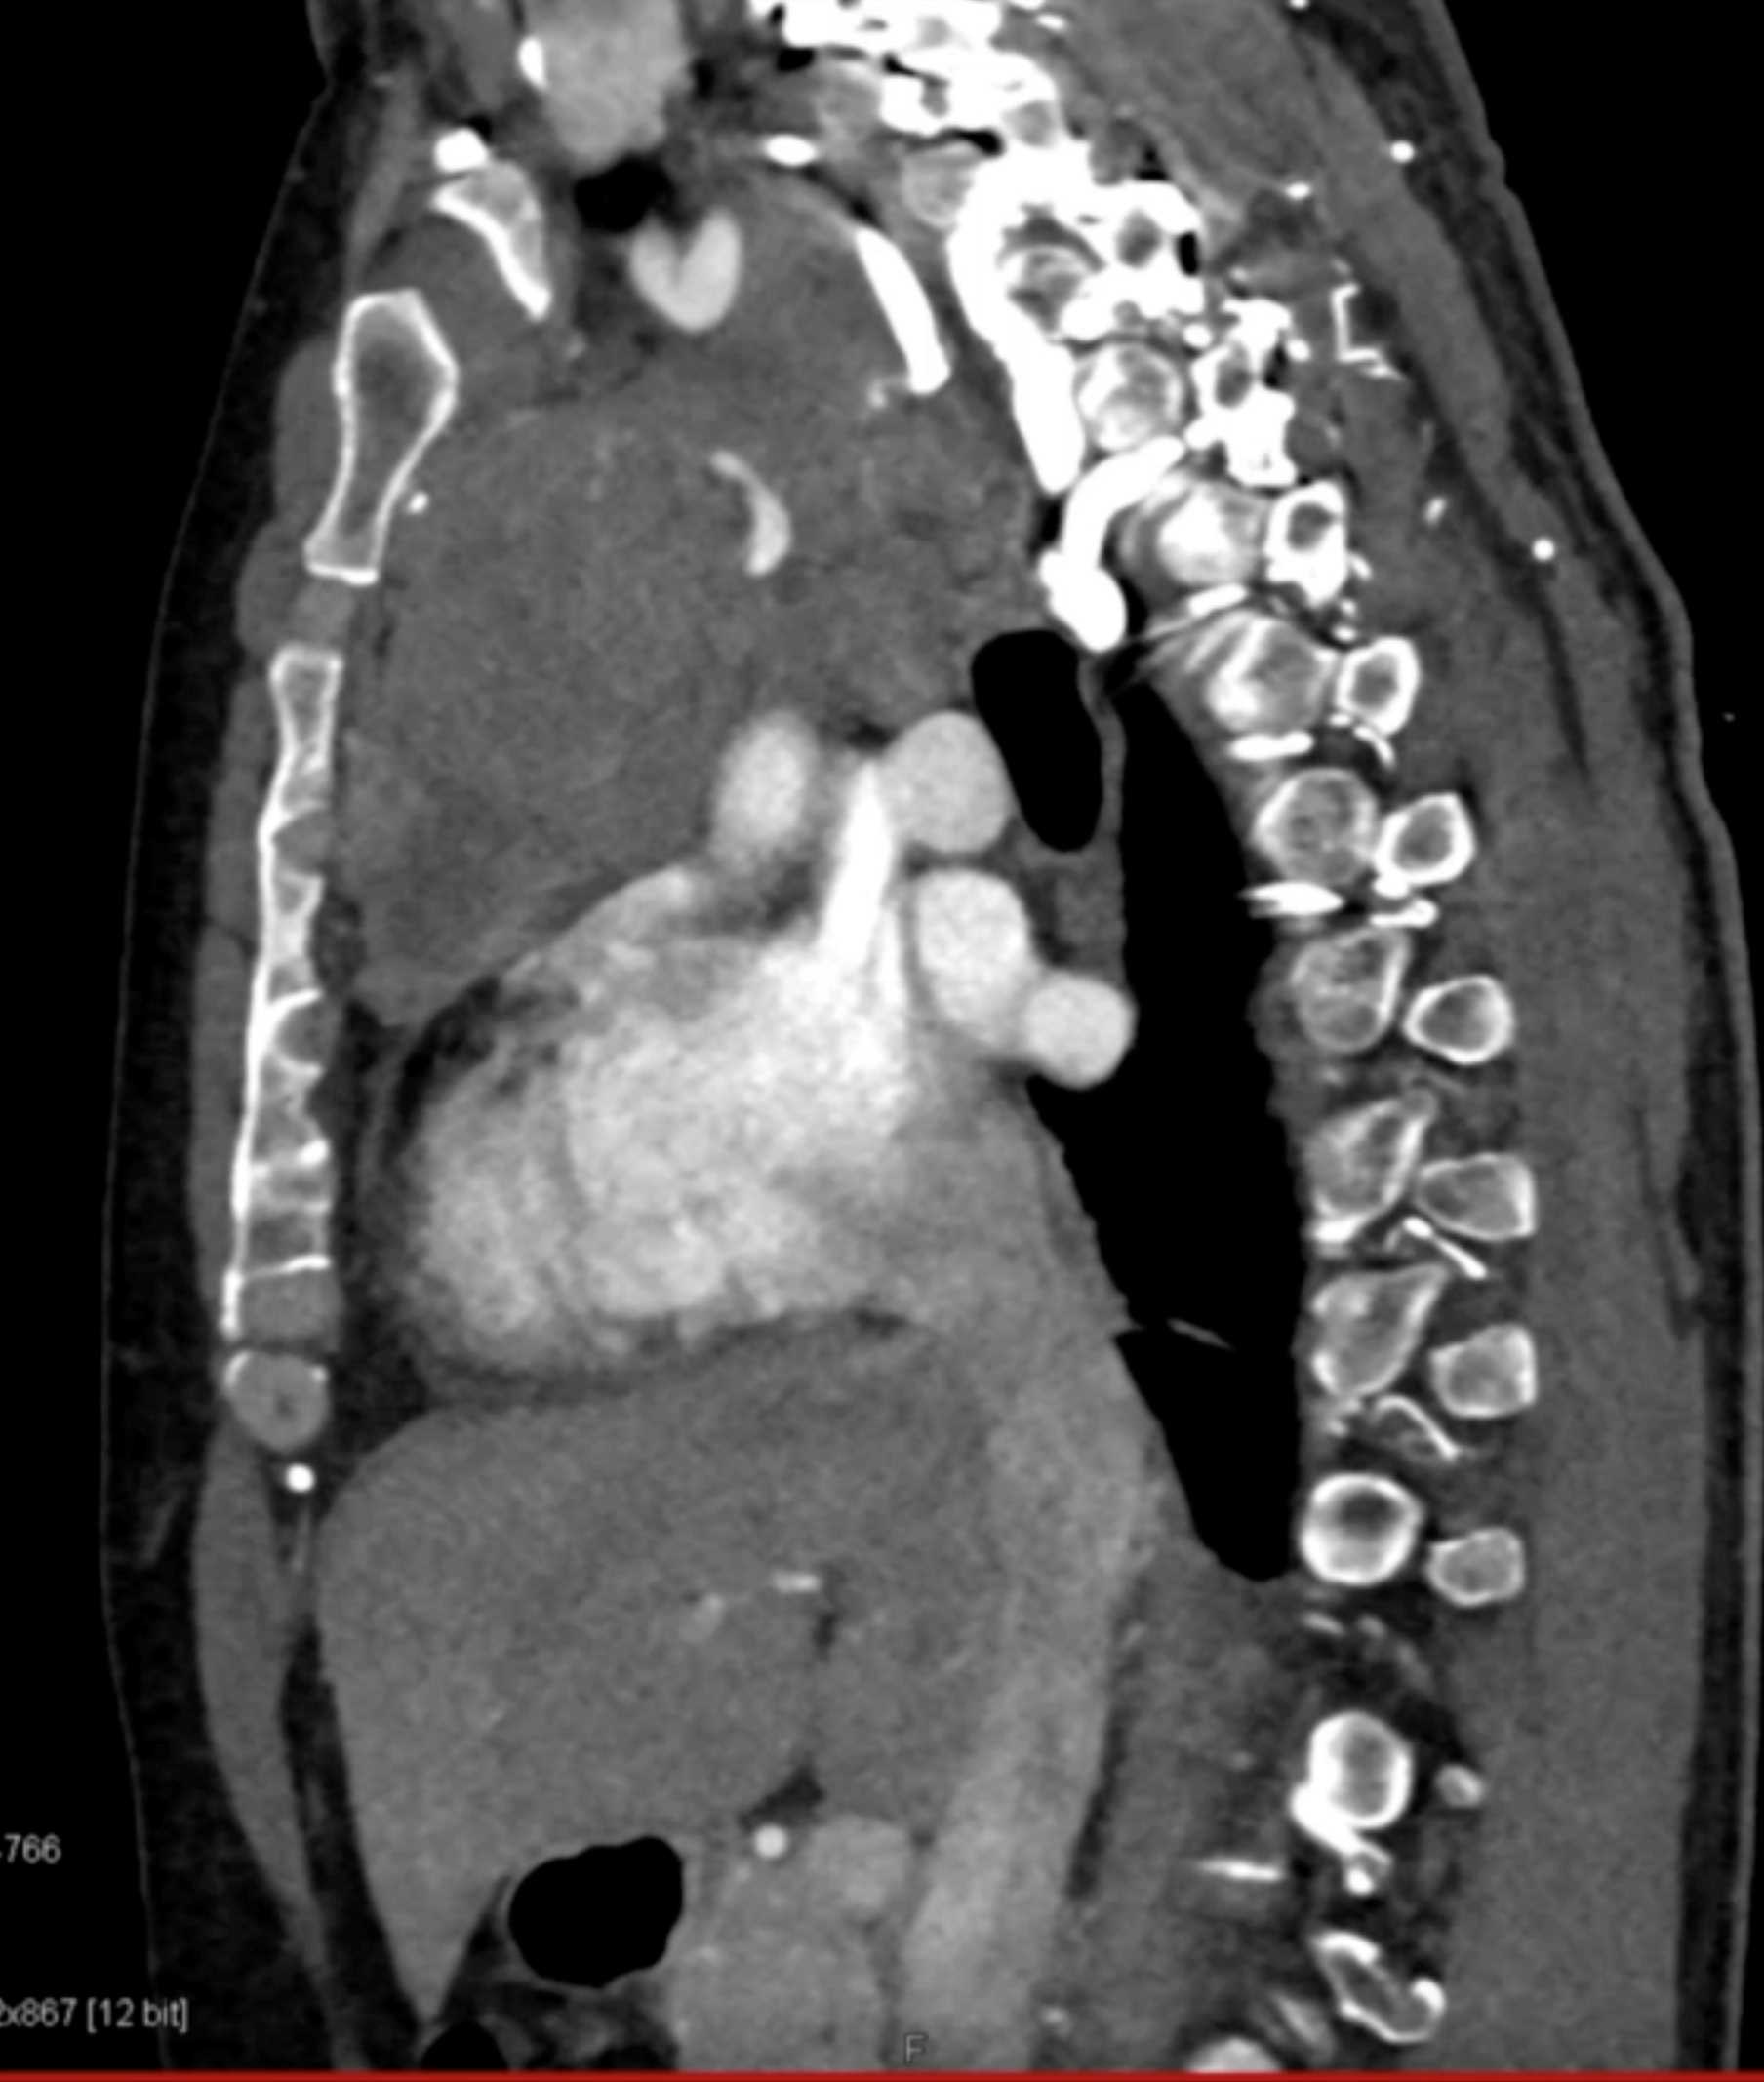

Thymic Carcinoma